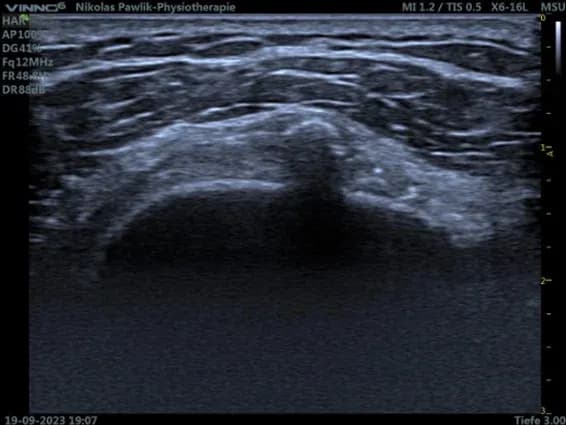

Mittelhandnerv

Dies ist die Darstellung eines leicht vergrößertem Nervus medianus bei

Karpaltunnelsyndrom